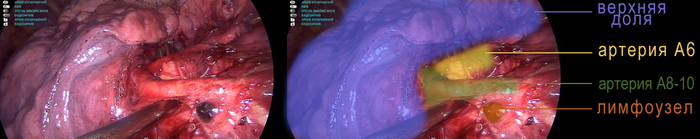

В данном случае секвестрация расположена в нижней доле легкого, то есть, в теории, надо удалять нижнюю долю легкого. Но мы решили попробовать сохранить шестой сегмент легкого, так он не вовлечен в процесс и, в приципе, при типичном строении сосудистого русла, его не так сложно оставить.

Далее в междолевой борозде нужно отыскать артерии. Артерию шестого сегмента нужно увидеть и  сохранить. Выделяем и прошиваем артерию, которая питает только 8-10 сегменты: